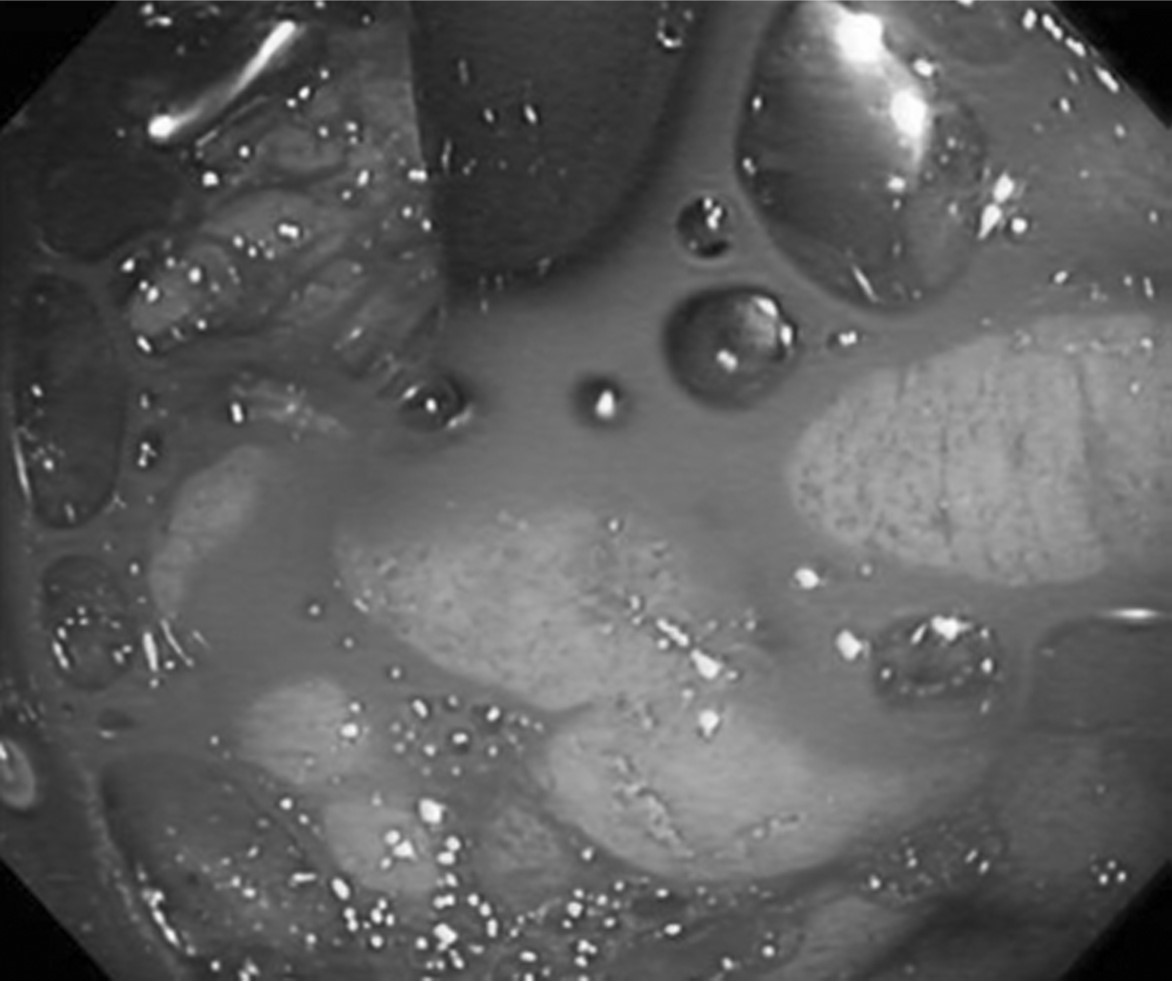

Fig. 2.

Endoscopy shows active gastric variceal bleeding. Endoscopic variceal ligation was failed due to massive bleeding.